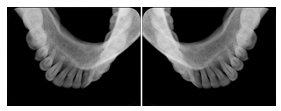

3. A patient in rural Minnesota experiences sudden vision loss and goes to a general ophthalmologist, who acquires OCT images and forwards them electronically along with a Structured Display to a retina specialist six travel hours away. The retina specialist is able to view the images in the standard layout that he is comfortable with, and to confirm that the patient has a choroidal neovascular membrane. He determines that is would be worthwhile for the patient to travel for treatment.

OCT Retinal Study with Cross Section and Navigation Structured Display